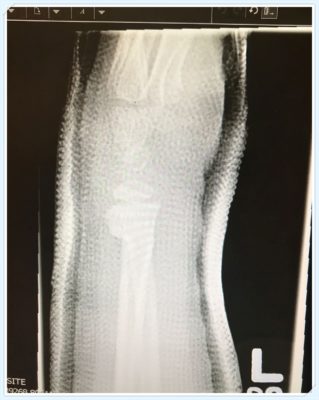

Today we had a follow-up with the fracture clinic and everything seems to be going ok. Her bone’s still aligned and the cast is in good shape. Best of all she’s been cleared to play in the first Lacrosse tournament this season.